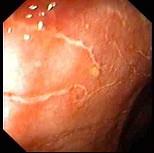

问题 男性,32岁,反复解黏液脓血便2年,查体:轻度贫血貌,心肺腹未见异常,大便常规示红细胞(++),白细胞(++),内镜图片如下,诊断 ( )

选项 A、溃疡性直肠炎 B、直肠癌 C、放射性肠炎 D、慢性结肠炎 E、直肠炎

答案 A